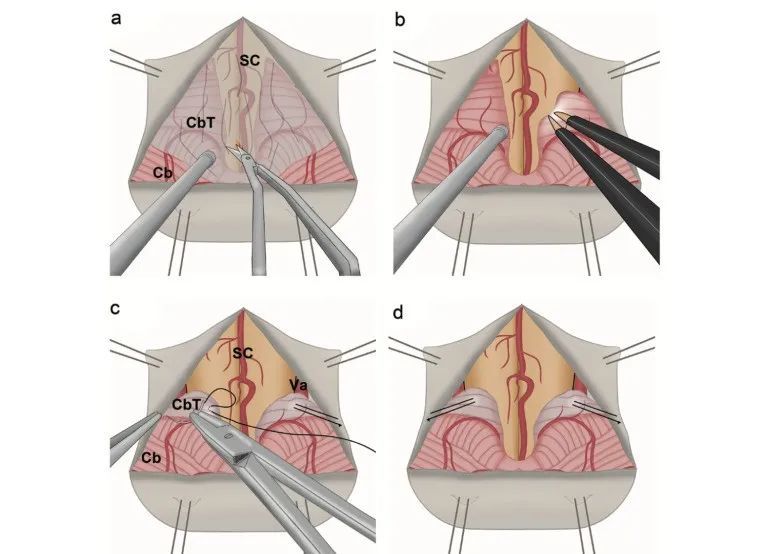

在PFDD中,小脑扁桃体主流的处理技术以电凝回缩和部分切除为主。但存在固定效果不确切,临床症状反复,二次手术风险等诸多不足。为改进该手术方式,我中心在国内和国际上率先提出了在后颅窝减压重建的处理上,采用电灼进行小脑扁桃体塑形后丝线悬吊的方法,即小脑扁桃体塑形悬吊术(图2)。

与常规的小脑扁桃体切除法或电灼相比,该新术式具有降低术后颅内出血风险、减少瘢痕组织蛛网膜粘连、预防小脑扁桃再次下垂等优势,能够更有效的改善患者的临床症状并且不增加额外的并发症风险。

图2. 小脑扁桃体塑形悬吊术示意图。a)松解蛛网膜粘连;b)双极电凝电灼小脑扁桃体进行塑形;c)丝线悬吊小脑扁桃体;d)双侧悬吊后效果图。